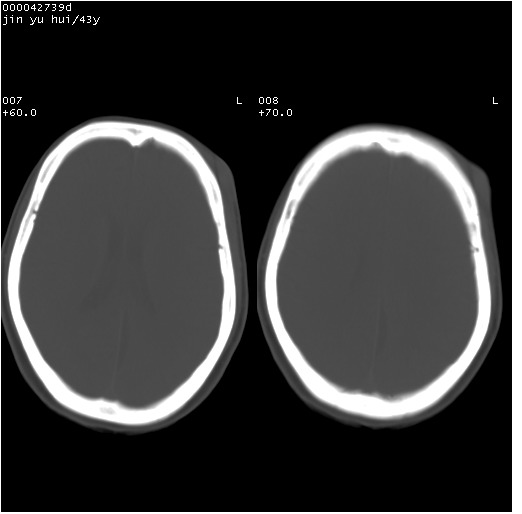

患者 女,43岁。头部外伤26天,经住院治疗,现头痛减轻。申请ct复查,了解颅内情况。

临床诊断:2级脑外伤。

颅脑ct轴位平扫(层厚、层距均为10mm),图像如下:

纵裂旁硬膜下水瘤,左额部头皮肿胀

大脑镰左旁慢性硬膜下血肿.左额部头皮血肿.